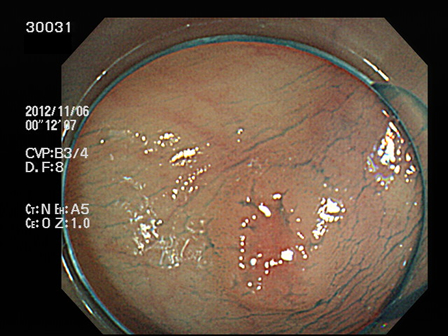

上記100名より抽出した平坦・陥凹型腺腫(=癌化の危険が高いが見落としやすい病変)の内視鏡写真

30001 30005 30008 30014 30016 30019 30020 30022 30023 30024 30025 30026 30027 30028 30029 30031 30033 30034 30036 30038 30044 30045 30047 30049 30051 30053 30055 30056 30057 30058 30059 30060 30066 30069 30072 30073 30074 30076 30077 30078 30079 30080 30081 30082 30083 30084 30085 30087 30088 30092 30097 30098・・・・・・・の52名